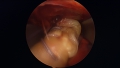

Nous avons décrit une technique endoscopique mini-invasive que nous avons publiée dans l'American Journal of Sports Medicine. Elle s'avère sûre et reproductible dans ses résultats avec un taux plus faible de complications. C'est notre technique de choix de réparation de ces lésions du biceps, notamment chez le sportif de haut niveau comme les rugbymen.